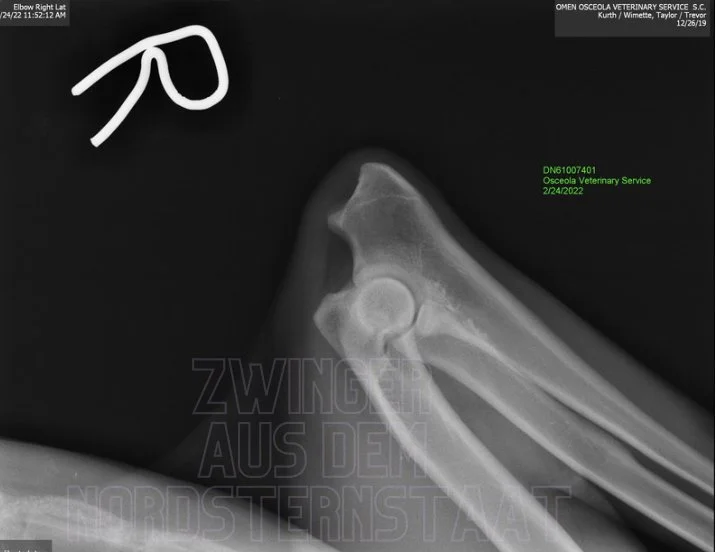

Omen is OFA Normal Elbows